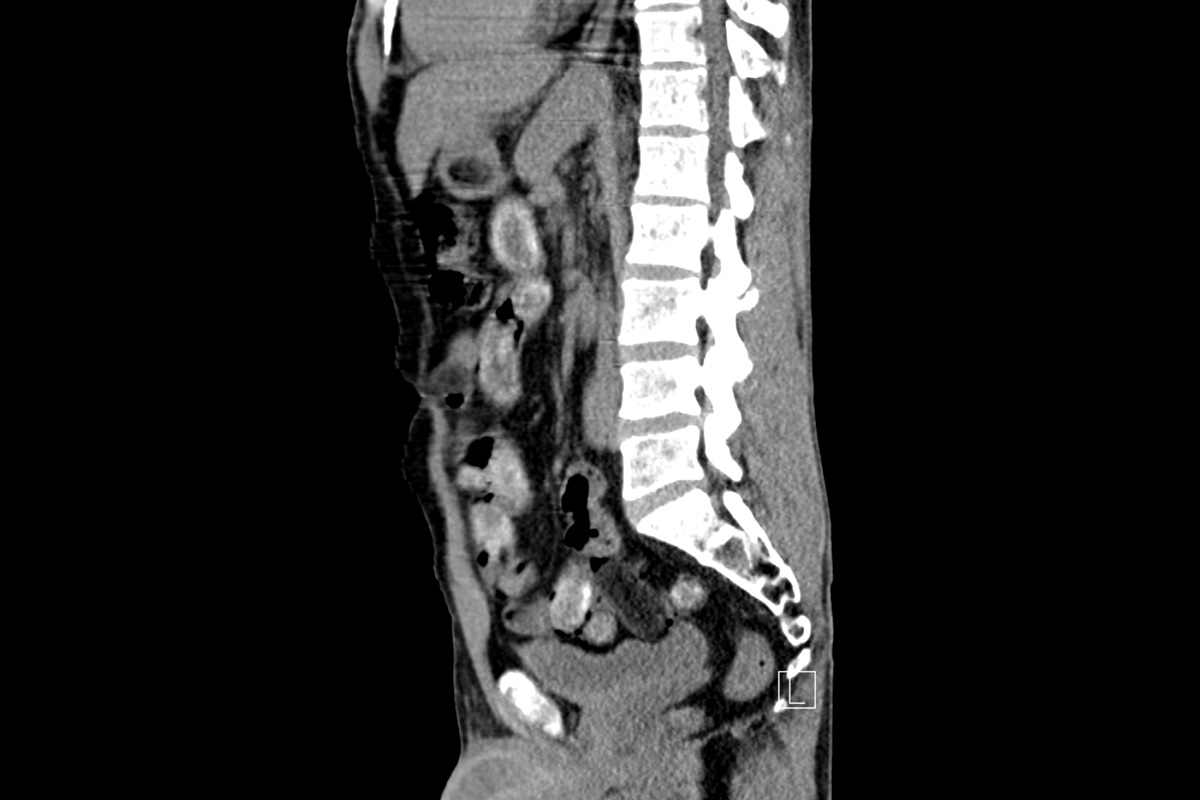

Hier verteilen sich die Bodypacks im Magen und Darm. (Bildquelle: Hauptzollamt Köln)

Mit Röntgenaufnahmen bestimmen die Zöllner die Menge der Bodypacks. (Bildquelle: Hauptzollamt Köln)